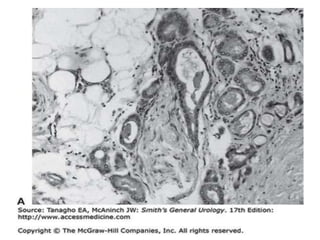

Histology Of Prostate Gland

• Peripheral zone:

Histology Of ProstateGland • Peripheral zone: • Upto 70% of prostate • Surrounds distal urethra • Accounts for 70-80% of prostatic cancer • Central zone: • Upto 25% of prostate • Surrounds ejaculatory duct • Accounts for 2.5% of prostate.cancers • Transition zone: • Upto 5% of prostate area • Surrounds proximal urethra • Accounts for 10-20% of prostatic cancers